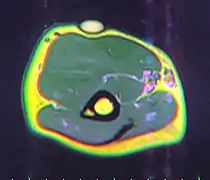

- MRI showing lipoma of the arm